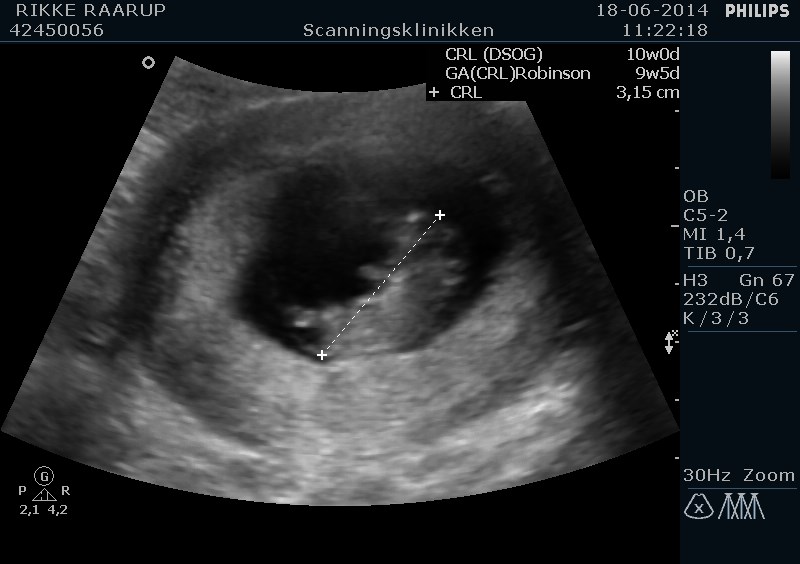

HELDIGVIS så vi den fineste lille babyspire. Målene passede til min udregning - 10+3. Vi så et fint hjerteblink og fin gennemstrømning. Grundet vores historie satte hun hjertelyd på Jep - crybaby

Vedhæftede fotos (klik for at se i fuld størrelse)